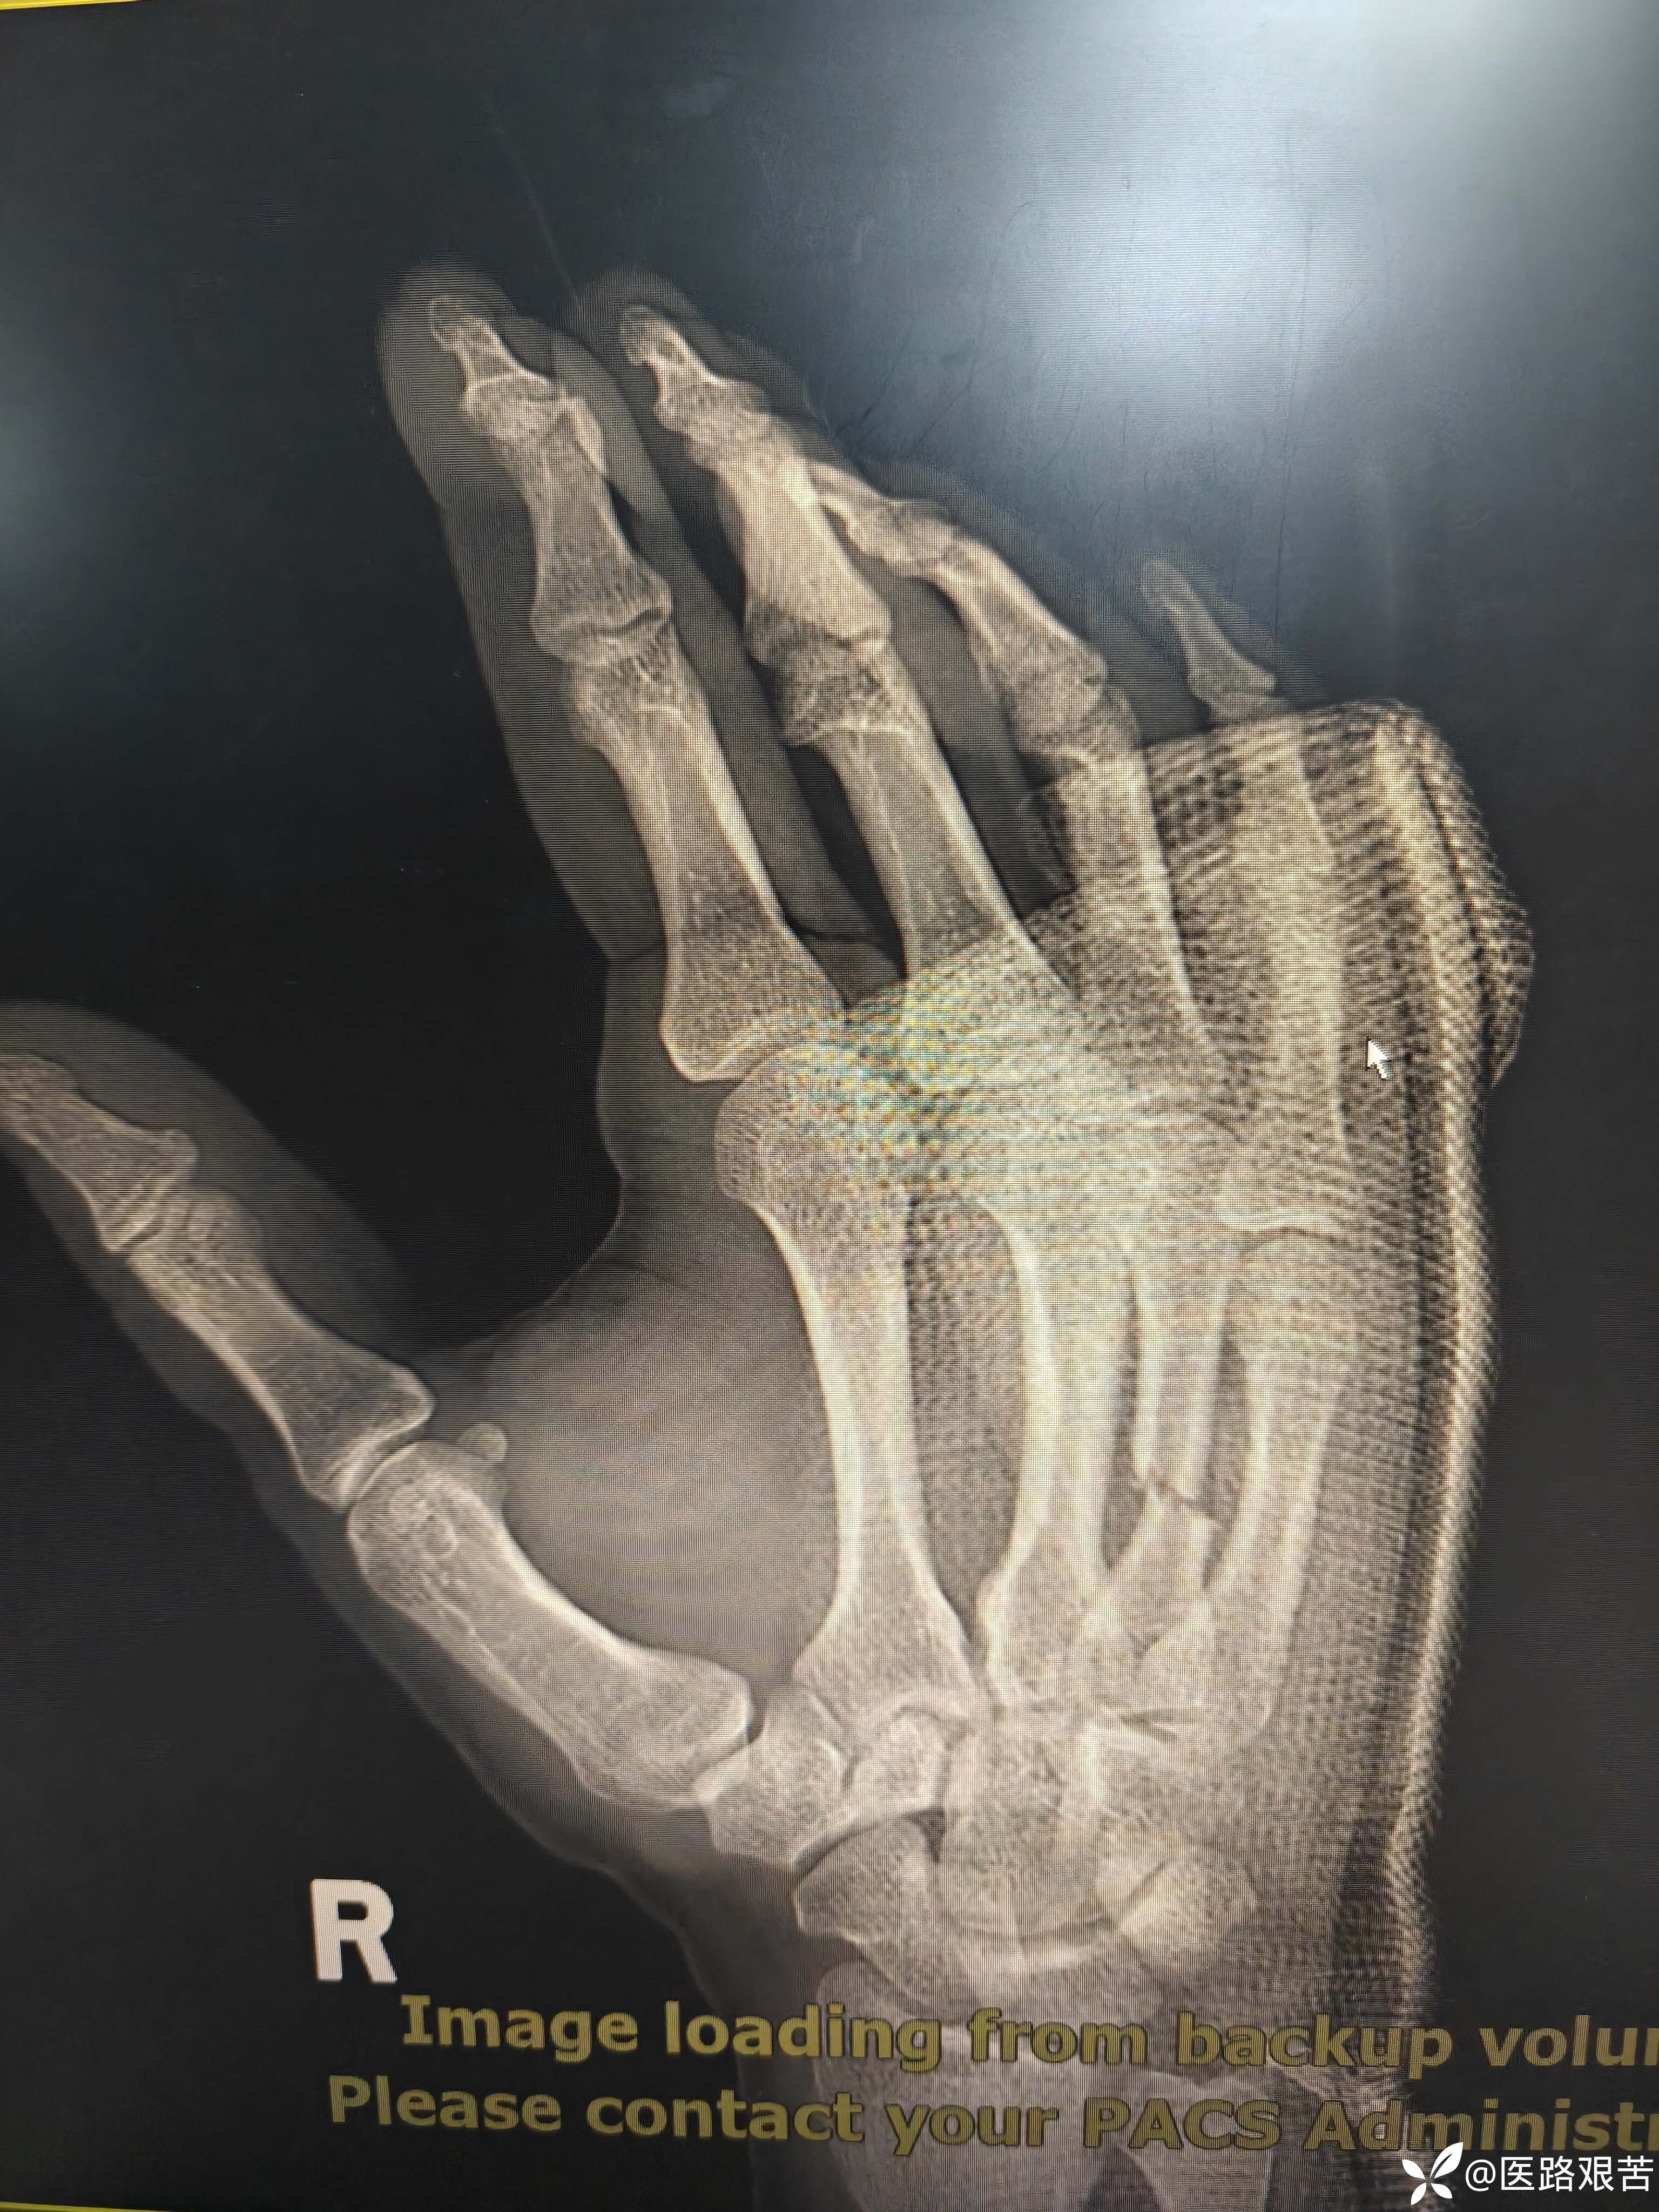

患者,男,32岁,外伤摔倒致右手第四掌骨骨折,伤后1天就医,手法复位石膏固定后,表示骨折立线正,可接受,愈合时间稍长,患者要求解剖复位,并希望早日活动。

受伤后DR

img